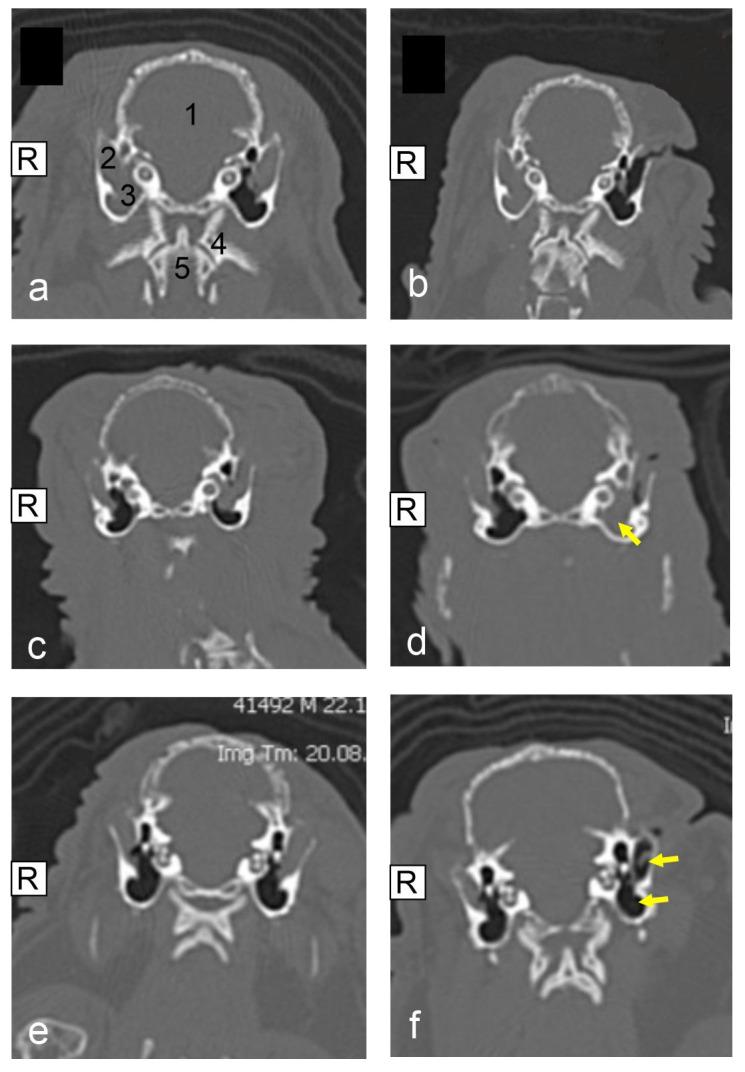

A soft tissue-filled external ear canal, sometimes also referred to as otitis externa in the veterinary literature, is a prevalent disease in pet rabbits, especially in lop-eared pet rabbits. The authors describe the clinical findings, diagnostic workup, therapy, and outcome of pet rabbits treated surgically for a lateral ear canal ablation (LECA). For the time period between 2015 and 2023, the medical records of two veterinary clinics were evaluated retrospectively. A total of 25 pet rabbits, diagnosed via computed tomography (CT) scans with a soft tissue-filled external ear canal and (if present) middle ear, were identified. All the pet rabbits were evaluated as lop-eared pet rabbits and all were treated surgically using the same surgical technique, LECA. In accordance with Richardson et al., we categorized the different ear filling levels by using the grading system that was established in 2019. The mean follow-up period was 19 days, and in one case complete wound healing was not reached within 131 days after surgery. A total of 7/25 of the pet rabbits were evaluated with wound healing issues. Of the cases, 18/25 did not develop any recurrent ear diseases. Loss to follow-up was observed in 5/25 of the cases and recurrent ear diseases were identified in 2/25 of the pet rabbits. Progression of the ear disease was detected in four cases. CT post-operative images were acquired for 14/25 of the pet rabbits. Based on this study, LECA can be considered a safe surgical method to treat soft tissue-filled external ear canals, especially in lop-eared pet rabbits. Nonetheless, thorough post-surgical management including wound control is critical for therapy success.

外耳道软组织填充,在兽医文献中有时也被称为外耳炎,是宠物兔中一种常见的疾病,尤其是在垂耳宠物兔中。作者描述了接受外侧耳道切除术(LECA)手术治疗的宠物兔的临床发现、诊断检查、治疗方法及结果。对2015年至2023年期间两家兽医诊所的病历进行了回顾性评估。通过计算机断层扫描(CT)扫描,共确定了25只外耳道有软组织填充且(如有)中耳也有病变的宠物兔。所有宠物兔均被评估为垂耳宠物兔,且均采用相同的手术技术LECA进行手术治疗。根据理查森等人的方法,我们使用2019年建立的分级系统对外耳道不同的填充程度进行分类。平均随访期为19天,有1例在术后131天内未实现伤口完全愈合。共有7/25的宠物兔存在伤口愈合问题。其中,18/25的病例未出现任何耳部疾病复发。25例中有5例失访,2/25的宠物兔发现耳部疾病复发。在4例中检测到耳部疾病进展。对25只宠物兔中的14只进行了术后CT图像采集。基于这项研究,LECA可被认为是治疗外耳道软组织填充的一种安全手术方法,尤其是在垂耳宠物兔中。尽管如此,包括伤口控制在内的全面术后管理对于治疗成功至关重要。